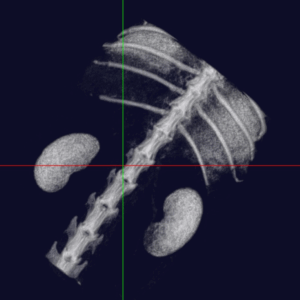

中・小型動物用3DマイクロCT

CTとはコンピューター断層撮影(Computed Tomography)の略で、X線を用いて身体の横断像(輪切り)を撮影することが出来ます。立体3D画像が得られるのも特徴で、主に骨格の異常や臓器系の異常部位、腫瘍性病変の把握に利用されます。

当院では「中・小型動物用3DマイクロCT」を導入しています。エキゾチックペットから猫・小型犬まで撮影可能です。

高画質で立体的に見ることで、レントゲンや超音波検査では分からない病態の診断や、構造が複雑な部位の細かい評価が可能です。

体の断層像に加え立体3D画像の作成が可能

事前に病変部位やその周囲の臓器との関係性を把握することで、より正確で安全な外科手術につながります。

下顎骨 骨折

猫 頭部CT

犬 椎間板ヘルニア

フェレット 血管造影